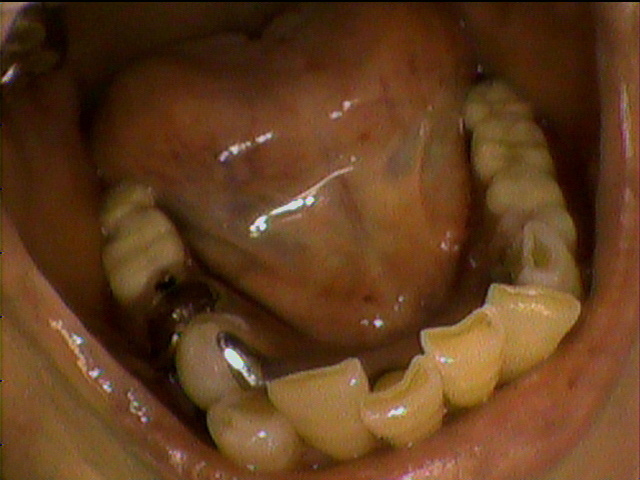

上の入れ歯がこわれてしまって、来院されました。のこっている上の前歯の6本分がつながったブリッジは歯ぐきが根元ではれていてぐらぐら状態。全く噛む場所がありません。

診断すると、残っている前歯4本は歯の中がほとんどくさってしまっていました。

残念ながら前歯はすべて抜かなくてはならず、上の歯は総入れ歯としてまず治療用入れ歯を事前に準備することから開始しました。同時に歯ぐきの腫れの消炎処置をしました。

前歯のつながった歯を切り離し、同時に歯を抜き、その日にすぐに仮の入れ歯を装着することとしました。

顎の粘膜の調整をしながら経過し、上の入れ歯との噛み合わせを調整していきます。

顎の状態が良好になってきました

約2ヶ月後最終入れ歯を入れた状態です。

初診から最終調整まで、前歯がなくなってしまう見栄えが悪い事は一日もなく治療を進行することができました。

現在 右も左もしっかりと噛む事が出来ます。